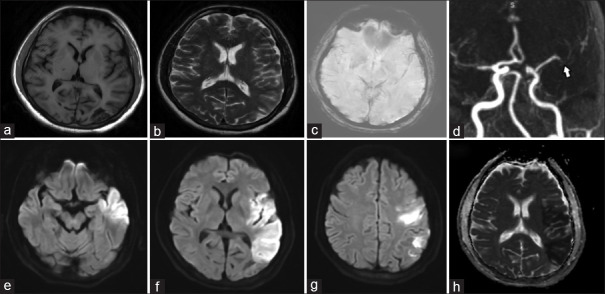

Arterial and Venous Infarcts: Dual Phenotypes of Dual Heterozygous MTHFR Gene Mutation.

动脉和静脉梗死:双杂合MTHFR基因突变的双重表型。